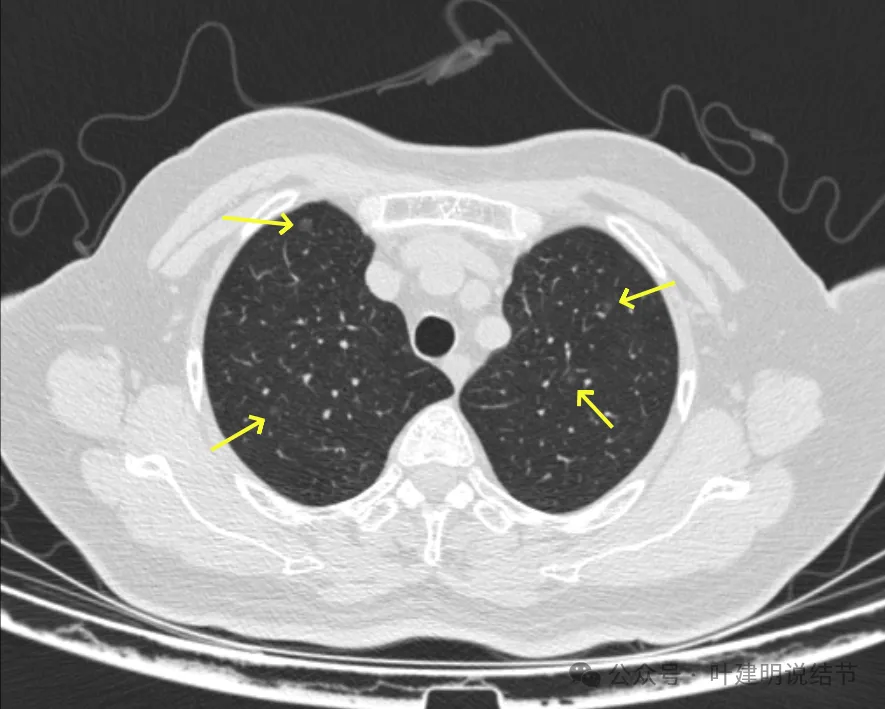

病灶1-4:两肺多处淡磨玻璃结节,密度低,散在,轮廓较清。

病灶11-14:两肺淡磨玻璃结节,轮廓较清。

病灶19-20:两肺淡磨玻璃结节,轮廓较清,小但边界清楚。

病灶21-22:两肺淡磨玻璃结节,轮廓较清。

病灶23-26:两肺微小淡磨玻璃结节,轮廓较清。

病灶27-30:两肺微小淡磨玻璃结节,轮廓较清。